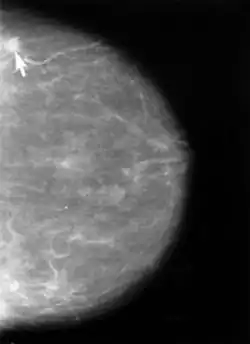

Für Männer werden beispielsweise regelmäßige Untersuchungen des Arztes auf Blut im Stuhl und das Abtasten der Prostata (siehe Prostatakrebs) durchgeführt, für Frauen ein Abstrich vom Gebärmutterhals (systematische Früherkennungsuntersuchung auf Gebärmutterhalskrebs) und Mammographie-Vorsorgeuntersuchungen (ab 50 Jahren) vorgenommen. Auch mittels genetischer Untersuchungen ist es möglich, bestimmte Krebsarten bereits im Frühstadium zu erkennen. Dieses Verfahren wird in der Praxis jedoch selten angewandt, da die Konzentrationen an Biomarkern des Tumors zu Beginn gering und näher an der Nachweisgrenze der Untersuchungsmethoden sind, wodurch falsch-negative Ergebnisse entstehen können.

Jede Selbstuntersuchung ist mit einem recht großen Fehlerrisiko behaftet. Knötchen in der Brust können harmlos sein, andererseits können Laien bösartige Brusttumoren erst ertasten, wenn sie eine bestimmte Größe (und somit ein höheres Tumorstadium) erreicht haben – und mit hoher Wahrscheinlichkeit schon metastasiert sind.